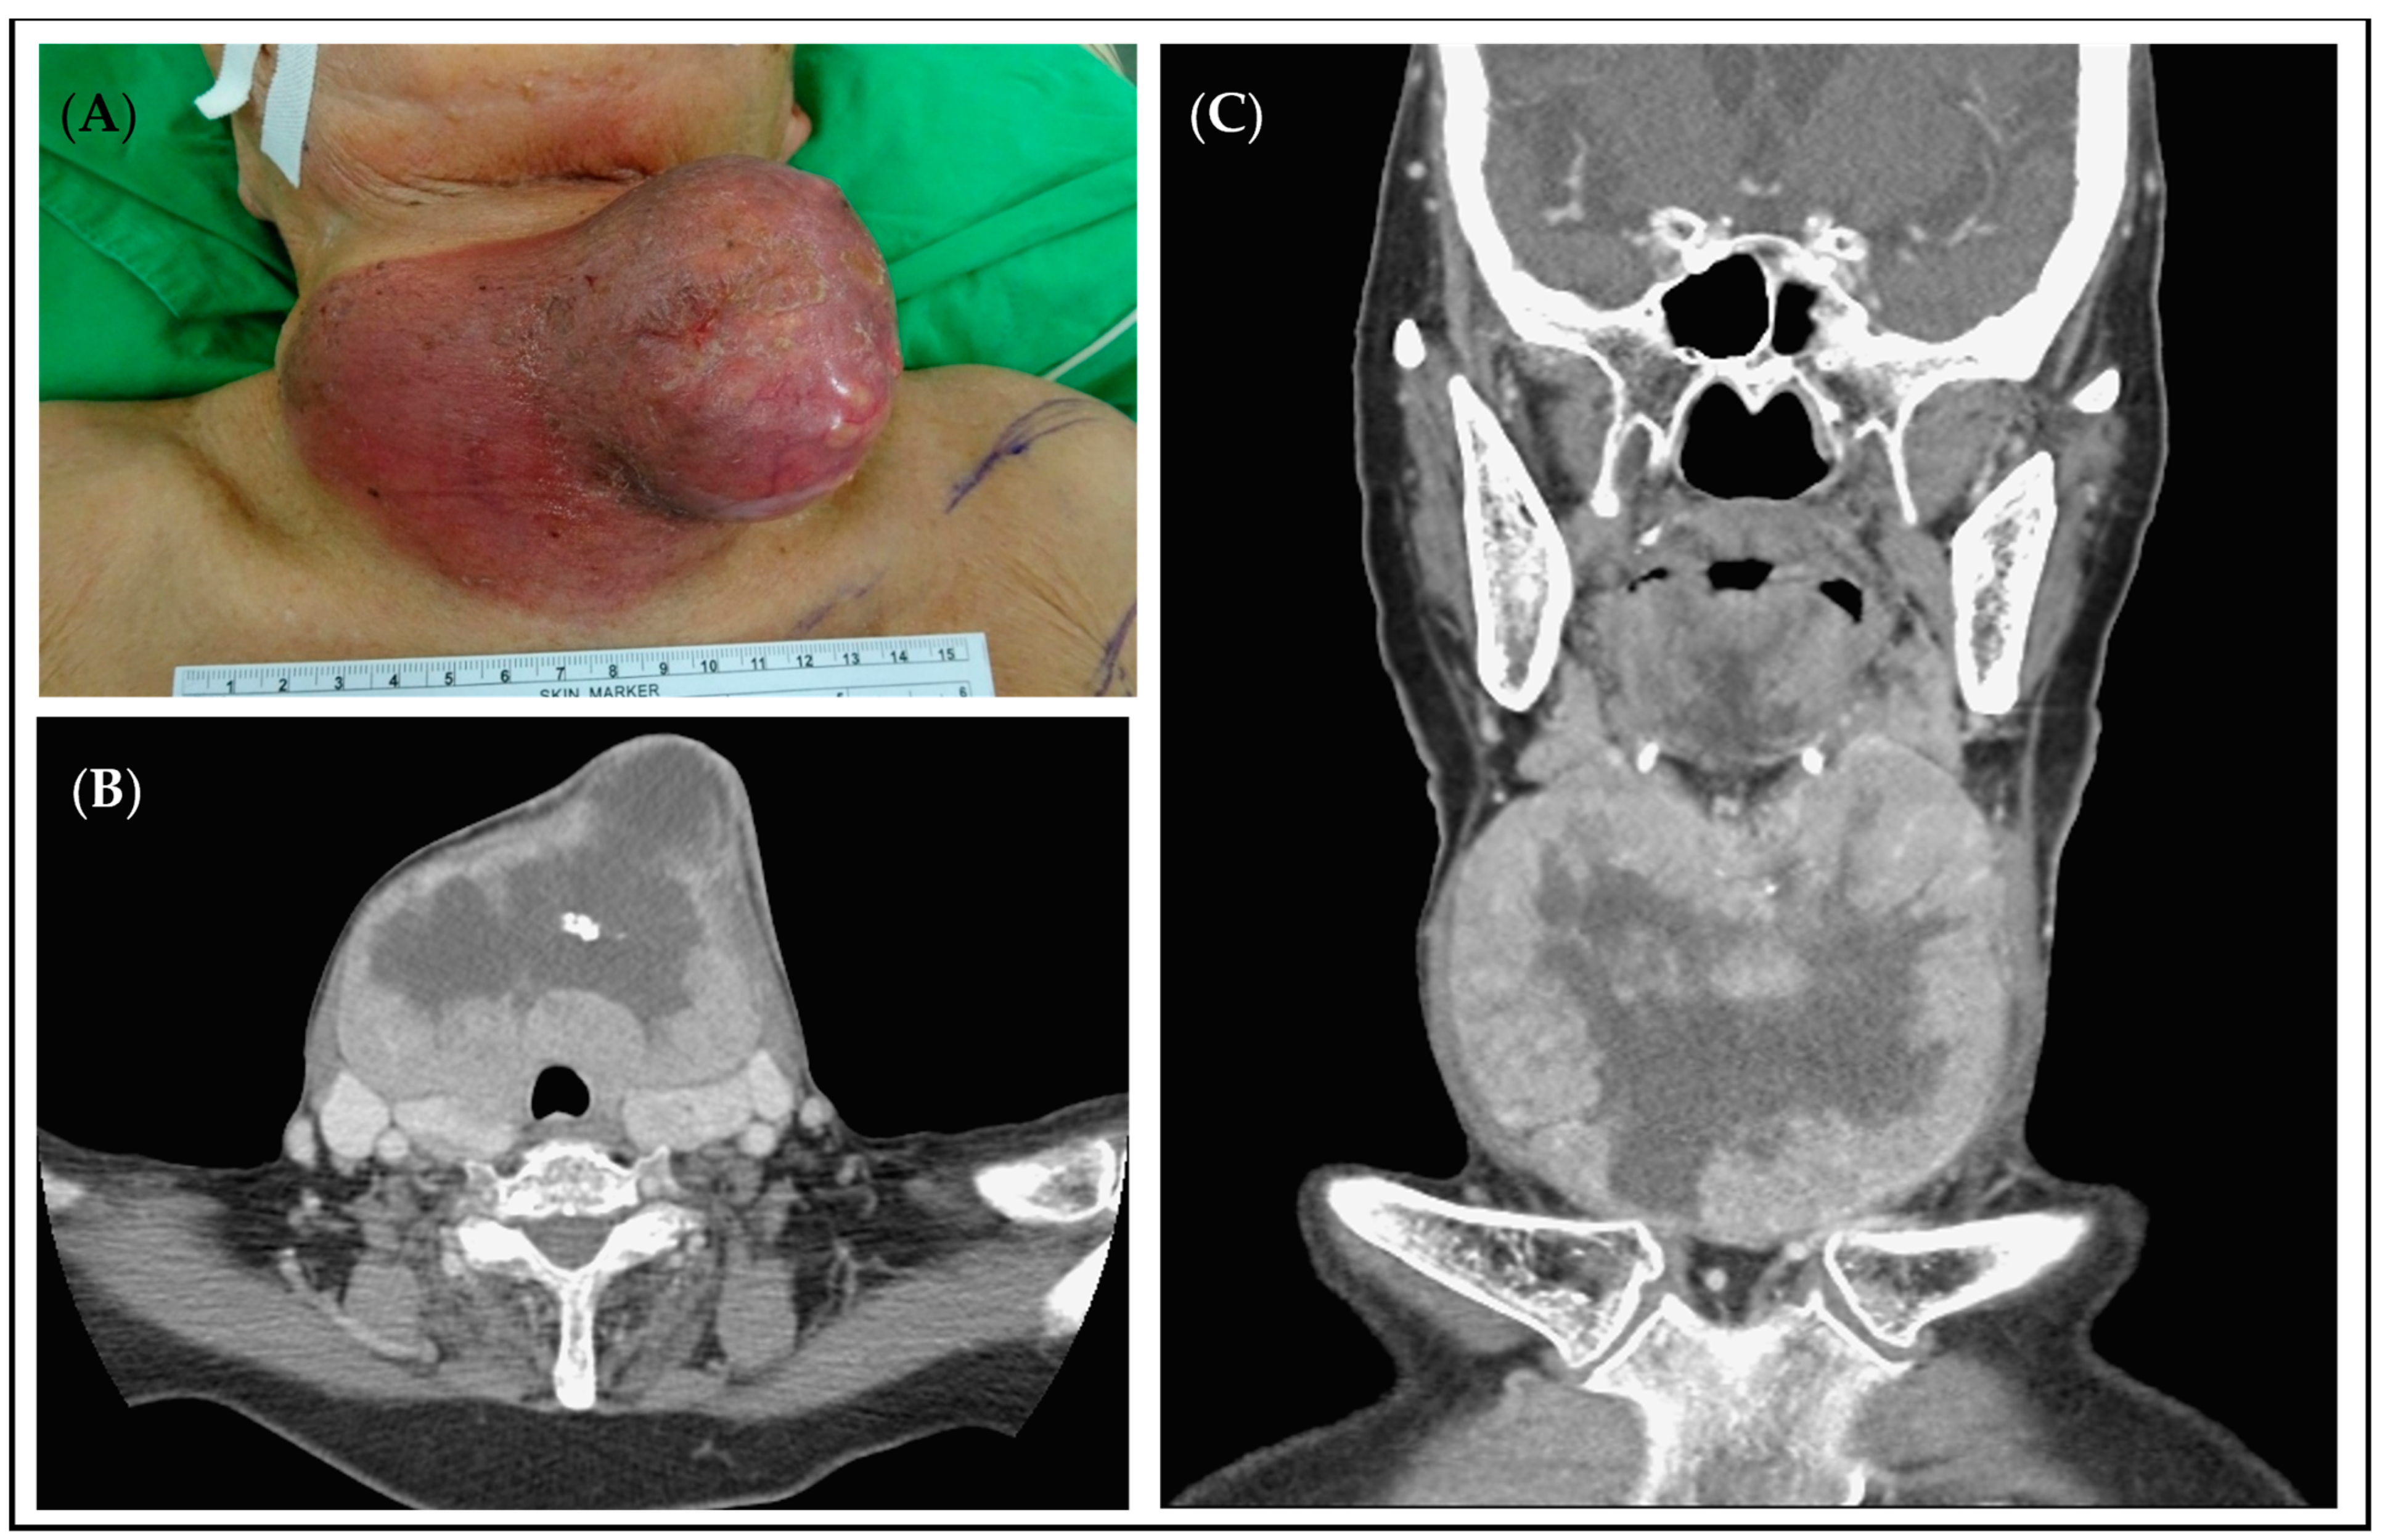

3.3.2. Case 2

| 2 | 92 | F | dependent | HTN | 0.2 | Rapid progression of neck mass with skin ulceration | Endocrinologists | Squamous cell carcinoma | Total thyroidectomy + PMMC flap | 350 | Transient hypocalcemia | 13 * | 28 ǝ |

| 2 | 92 | F | poorly to undifferentiated carcinoma with prominent squamous differentiation, bilateral | Follicular neoplasm of uncertain malignant potential, left | 10.6 | 8 | 510 | 227.8 | Unifocal | nil | nil | nil | Present |